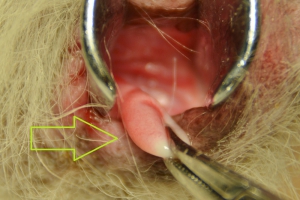

子宮内の病変も膣と同様の理由で発生するものと考えられます。このポリープは黄色矢印で子宮内腔に「栓」をするような状態になり子宮水腫の原因となっていたものです。そのすぐ下にも小さな病変が確認できます。